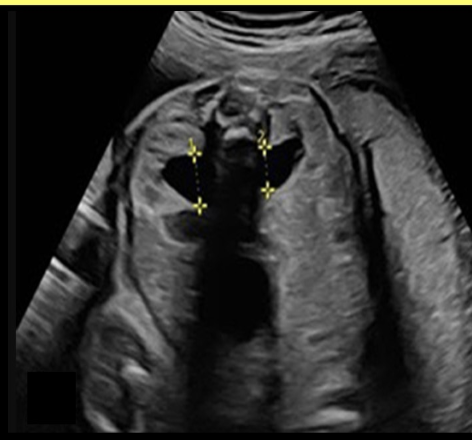

when fetal hydronephrosis is suspected, how is it properly documented by US

.

a) coronal image of both kidneys, measure minimum diameter of dilation

b) transverse image w/fetal spine at 12 or 6 o’clock, measure the minimum diameter of dilation

c) transverse image w/fetal spine at 9 or 3 o’clock, measure maximum diameter of dilation

d) transverse image w/fetal spine at 12 or 6 o’clock, measure the maximum diameter of dilation